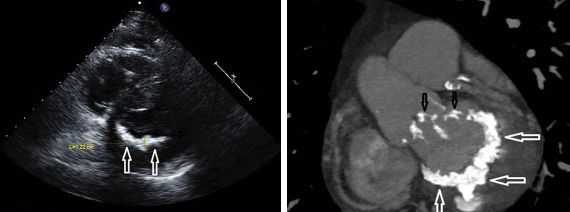

- Эхокардиография. Ультразвуковое исследование сердца — ведущий метод диагностики врожденных аномалий, характерных для синдрома. При осмотре удается визуализировать структурные изменения органа, оценить его функциональные возможности. Для уточнения диагноза применяется рентгенография ОГК.

В возрасте 15 лет после консультации в генетическом центре ребенку был поставлен диагноз: синдром Холта-Орама. При эхокардиографическом исследовании выявлены пролапсы митрального, трикуспидального клапанов и клапана легочной артерии 1 степени.